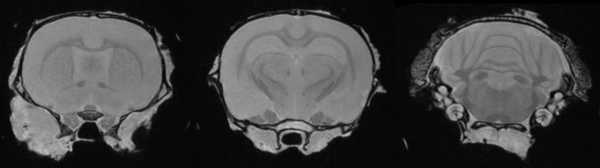

Neurobiology of mouse brain: T2- weighted images of a mouse brain. Image Credit: Scintica Instrumentation Inc

Epilepsy in the rat brain: T2- weighted images of a rat brain 48 hours after induction of epilepsy. Image Credit: Scintica Instrumentation Inc

T2- weighted images of a mouse brain. Image Credit: Scintica Instrumentation Inc

T2- weighted images of a rat brain 48 hours after induction of epilepsy. Image Credit: Scintica Instrumentation Inc